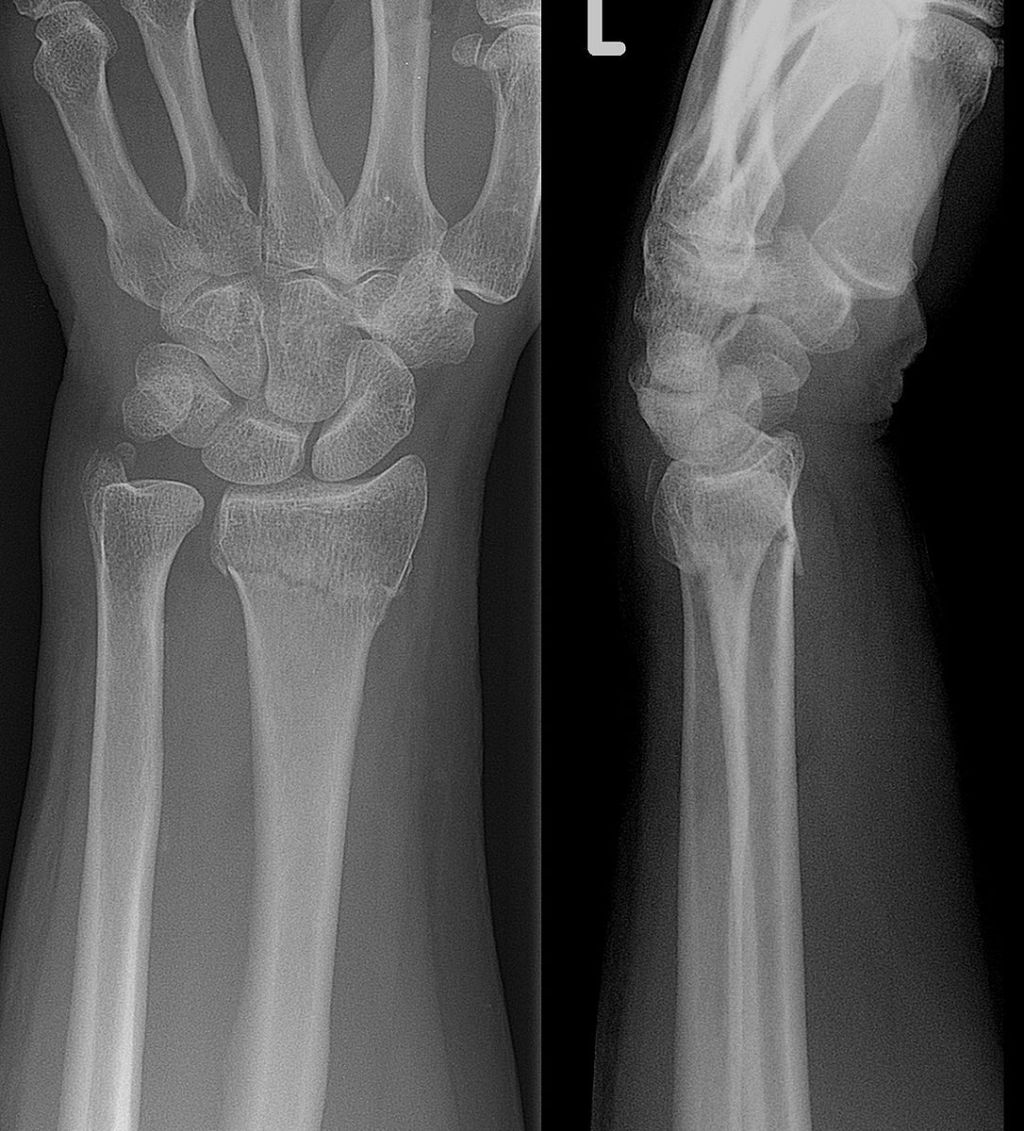

What is a Colles fracture?

A Colles fracture occurs on the distal part of the radius, the larger of two bones in the forearm. This kind of fracture results from an individual falling on to their outstretched hand. It is more commonly found in older populations due to poor bone health, which leaves them more susceptible to breaks, but can also result from high impact collisions in sports which cause athletes to land on the hand and forearm. This fracture causes the radius to move upward to create an obvious and prominent deformity.

The deformity which results from the Colles fracture is referred to as “having a dinner fork presentation”. It is described this way because when fractured, the distal part of the radius moves upward creating an angle in the forearm near the wrist. The straight forearm, angled wrist, and curved hand, together form the image of a fork. Other ways an individual who has had a Colles fracture would present are as: having a history of a fall onto an outstretched hand, having swelling in the wrist or pain local to the wrist, a decreased ability to grasp and pick up objects, numbness, tenderness, bruising, or an angled deformity of the wrist.

Non-surgical treatment of a Colles fracture will occur if the fracture is less severe and not very painful. If the bone is still within its regular alignment, a cast or splint may be used to set the bone in place to heal in its regular alignment. A splint may be considered over a cast if you are less active, as more active people are at risk of re-injury in a splint. If the wrist and hand is likely to still be used, such as in a young person, or an athlete, a plaster cast will be used for roughly 6 weeks with regular check-ups from a doctor to keep an eye on the healing process. A more severe fracture will result in more regular check-ups. Your doctor may refer for an X-ray to assess bone healing. In some cases, if the bone is close to its normal position, a technique known as closed reduction will be performed. This is where a doctor will move the bone to its correct position and cast, without a surgical incision being made.